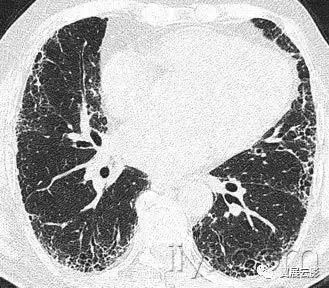

四十六、全腺泡性肺气肿

病理:全腺泡性肺气肿累及腺泡全部,累及次级肺小叶相对均一。主要累及下叶,该型肺气肿与抗胰蛋白酶缺乏有关。

CT:全腺泡性肺气肿表现为肺实质密度广泛性减低,病变肺的血管直径减小,严重的全腺泡性肺气肿可以与小叶中心性肺气肿并存并融合。乏特征性密度减低影与狭窄性闭塞性细支气管炎难以鉴别。与全小叶性肺气肿是同义词。